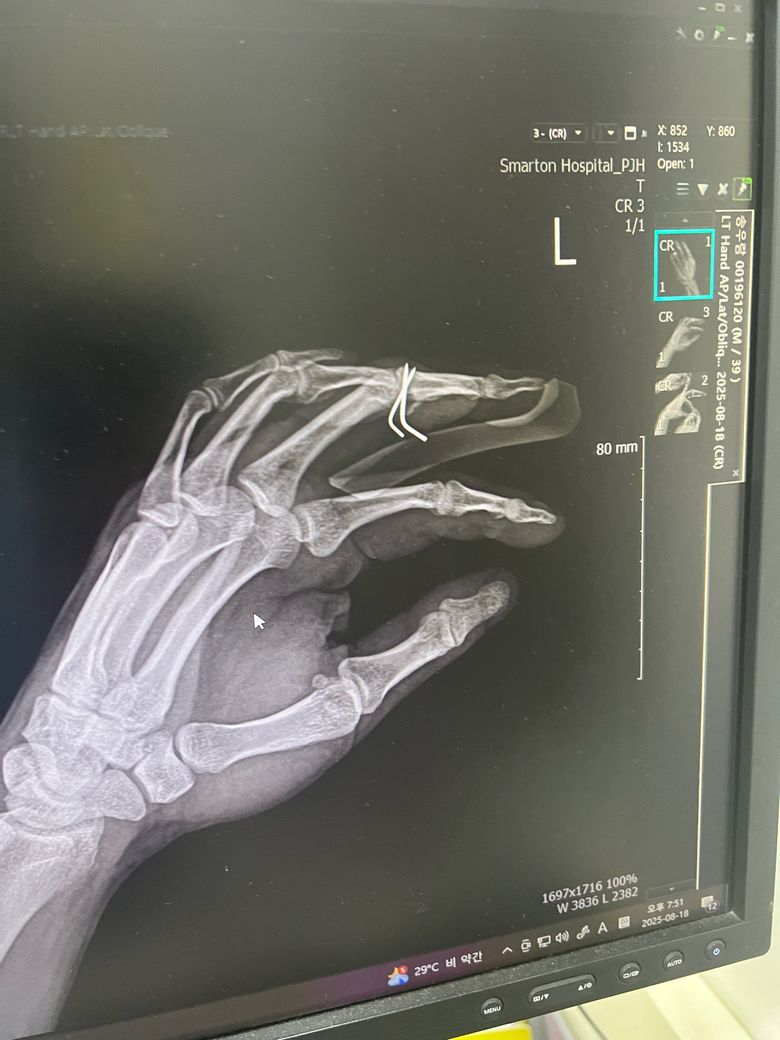

손가락 골절 수술 후 핀제거 했습니다.

1. 핀 제거를 하는데 원래 이렇게 아프게 뽑나요? 집도하신 원장님이 엑스레이 사진 빨간방향으로 잡아 땡기시더라구요.

그래서 제가 “그쪽방향이 아니다” 하니까 반대방향으로 빼던데 이사람이 집도한거 맞나요? 엑스레이도 봣으면서 왜 저 빨간방향으로 땡기는지.. 엄청아팟고 상처가 커졌습니다.

• 1번 째 사진

보통 핀을 뽑을 땐 약간의 통증이 동반되는것은 맞지만 핀을 박았을 때의 각도와 핀이 박힌 방향 그대로 빼는것이 맞지만 "ㄴ" 모양으로 되어있기에 다소 뽑을 때 통증이 동반됐을 가능성이 높습니다.